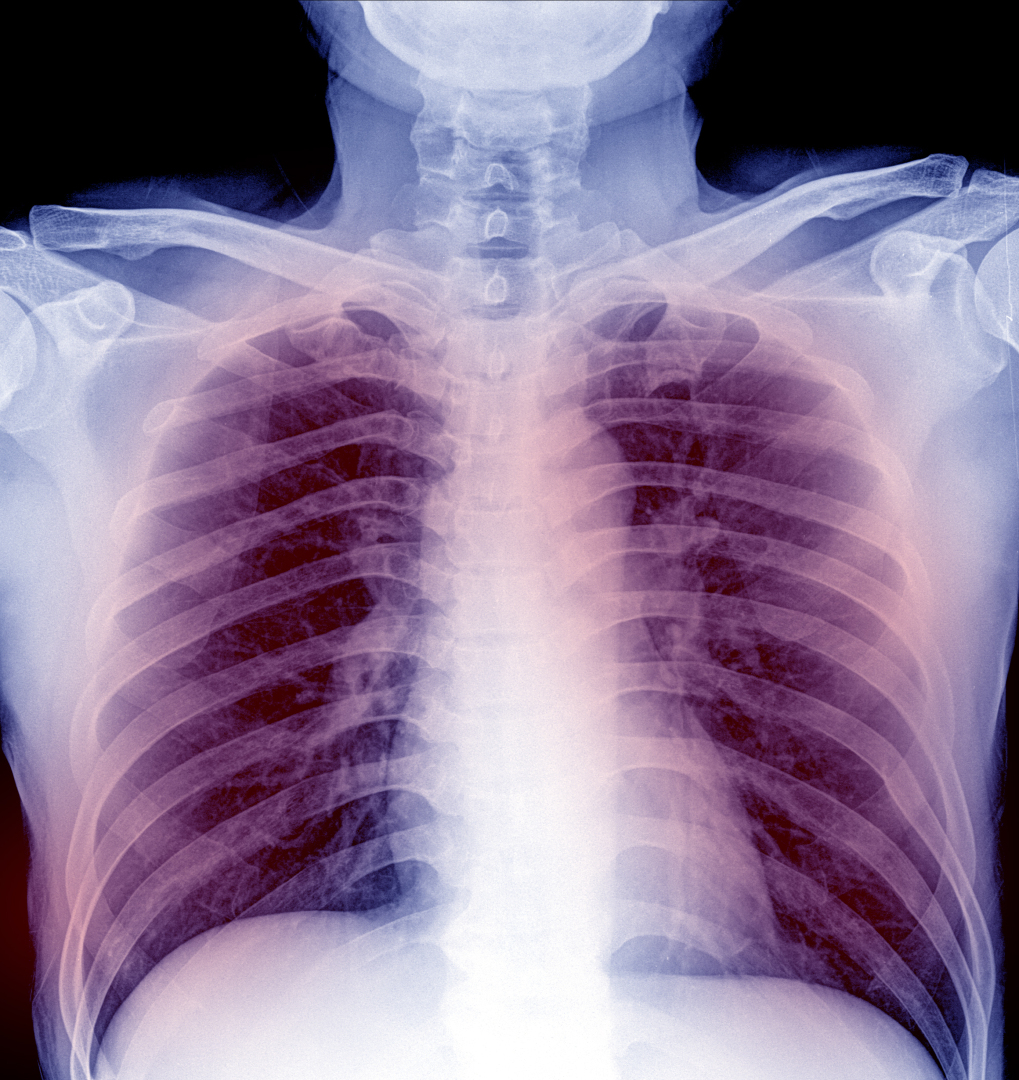

Acute respiratory distress syndrome (ARDS) is a serious lung condition that causes low blood oxygen. In ARDS, fluid builds up inside the tiny air sacs of the lungs, and surfactant breaks down. Surfactant is a foamy substance that keeps the lungs fully expanded so that a person can breathe. These changes prevent the lungs from filling properly with air and moving enough oxygen into the bloodstream and throughout the body.

The lung tissue may scar and become stiff. ARDS may develop over a few days, or it can get worse very quickly. The first symptom of ARDS is usually shortness of breath. Other signs and symptoms of ARDS are low blood oxygen, rapid breathing, and clicking, bubbling, or rattling sounds in the lungs when breathing. Infections are the most common risk factors for ARDS. These infections may include the flu, coronavirus or other viruses, and sepsis. The rate of death in the hospital is approximately 40% for ARDS patients.